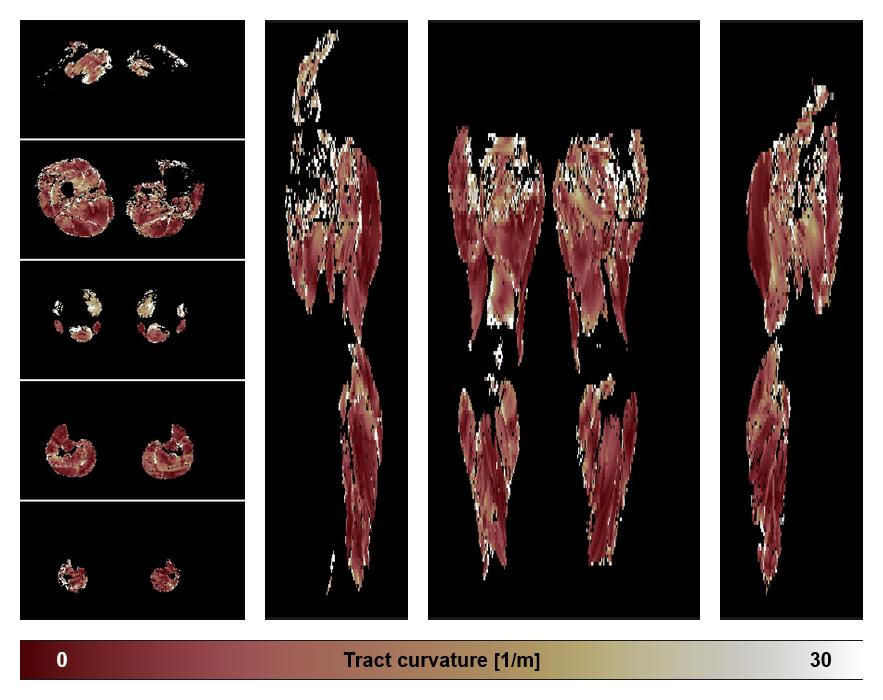

• Muscle fiber curvature map

Muscle fiber tract curvature map based on whole leg DTI based fiber tractography.